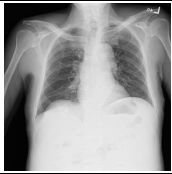

31.咳嗽 3 週